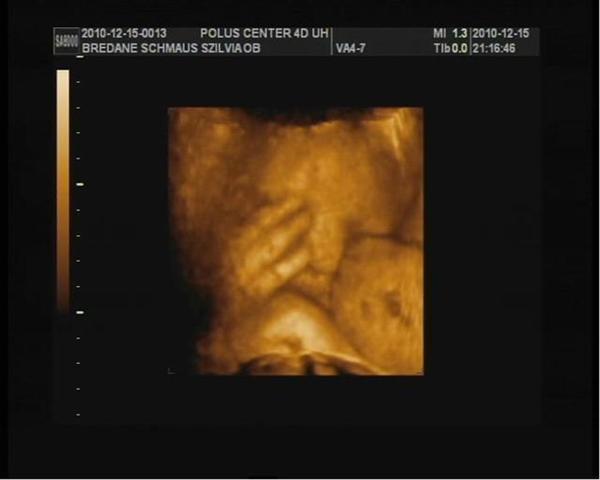

37.hét_01